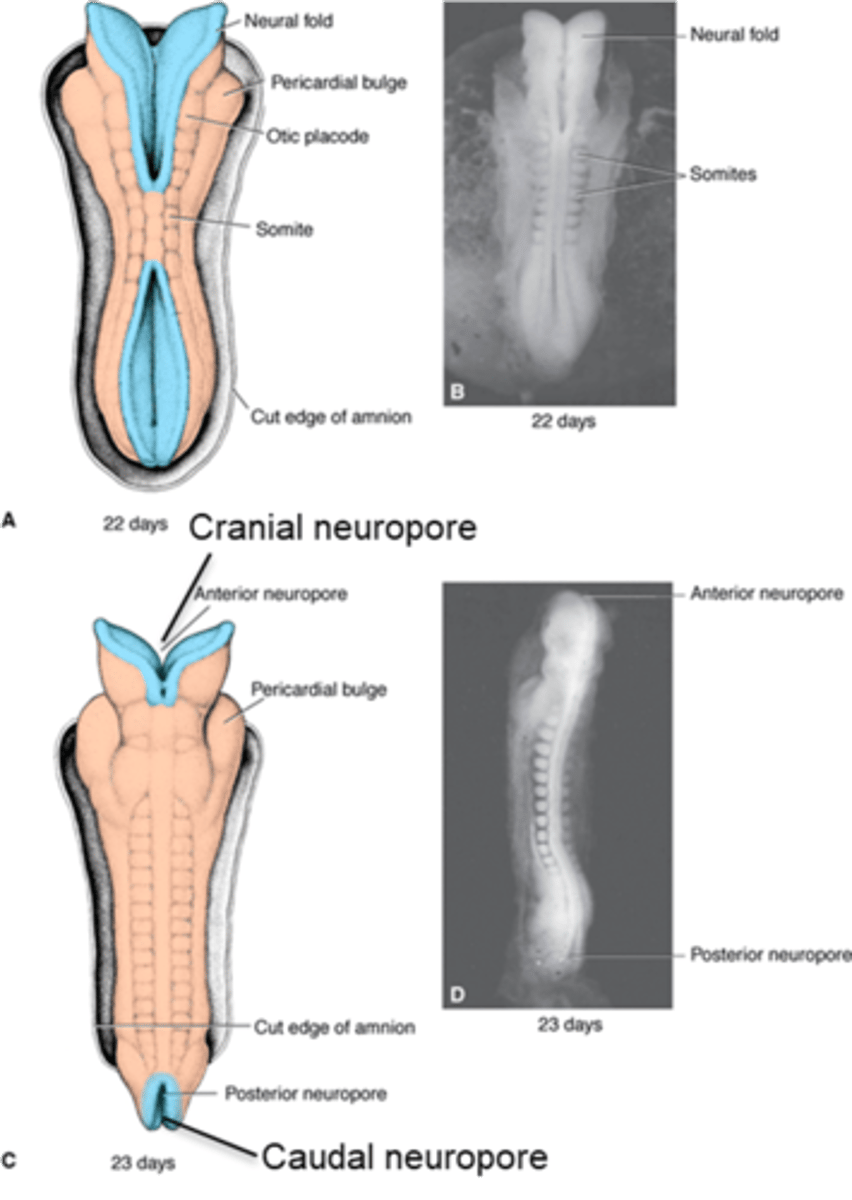

the CNS appears as a plate of thickened (endoderm/mesoderm/ectoderm) and forms the neural ________ induced by the ___________. the edges of the structure will then elevate and form the neural __________. the edges eventually approach the midline and fuse to form the neural _________.

ectoderm during the 3rd week

plate

notochord (thickening of mesoderm)

folds

tube

the fusion of the neural folds begins in the __________ region then proceeds ___________ and __________ to form the neural ________

cervical, cranially, caudally, tube

the (caudal/cranial) neuropore will normally close on day ____ before the (caudal/cranial) neuropore which closes on day ____

cranial, 25, caudal, 28

the narrow (caudal/cranial) portion of the neural tube will form the spinal cord while the broad (caudal/cranial) portion forms the brain vesicles

caudal, cranial

what neural tube defect is the most severe and caused by the failure of cranial neuropore to close leading to the absence of the major portion of skull and cerebral hemispheres?

anencephaly

what neural tube defect is caused by the failure of the caudal neuropore to close and varies in severity (like meningocele and myelomeningocele)?

spina bifida